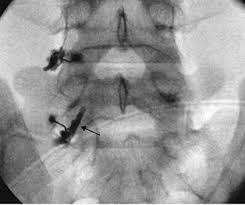

Επισκληρίδια έγχυσηΔιατρηματικό μπλοκΔιήθηση μεσοσπονδυλίων αρθρώσεωνΔιήθηση ιερολαγονίου άρθρωσης

Αρθροσκόπηση γόνατοςΡήξη μηνίσκουΡήξη χιαστούΑρθροσκόπηση ώμουΡήξη τενοντίου πετάλουΑκρωμιοπλαστικήΑρθροσκόπηση ποδοκνημικήςΑρθροσκόπηση Αγκώνα - Πηχεοκαρπικής

Συγκεκριμένα αναλαμβάνει περιστατικά παθολογίας όπως σκολίωση, αυχενικό σύνδρομο, σπονδυλική στένωση, τενοντίτιδες, αθλητικές κακώσεις, πλατυποδία, άκανθα πτέρνας, οστεοπόρωση κ.α.,χειρουργικές επεμβάσεις όπως διαδερμική χειρουργική, μεταταρσαλγία, βλαισό δάκτυλο, γαμψοδακτυλία, νευρίνωμα Μόρτον, πτώση μεταταρσίων, οστεοαρθρίτιδα, αρθροπλαστική γόνατος, αρθροπλαστική ισχίου, αρθροσκόπηση γόνατος, ρήξη χιαστού, ρήξη μηνίσκου, αρθροσκόπηση ώμου, σύνδρομο καρπιαίου σωλήνα κ.α.